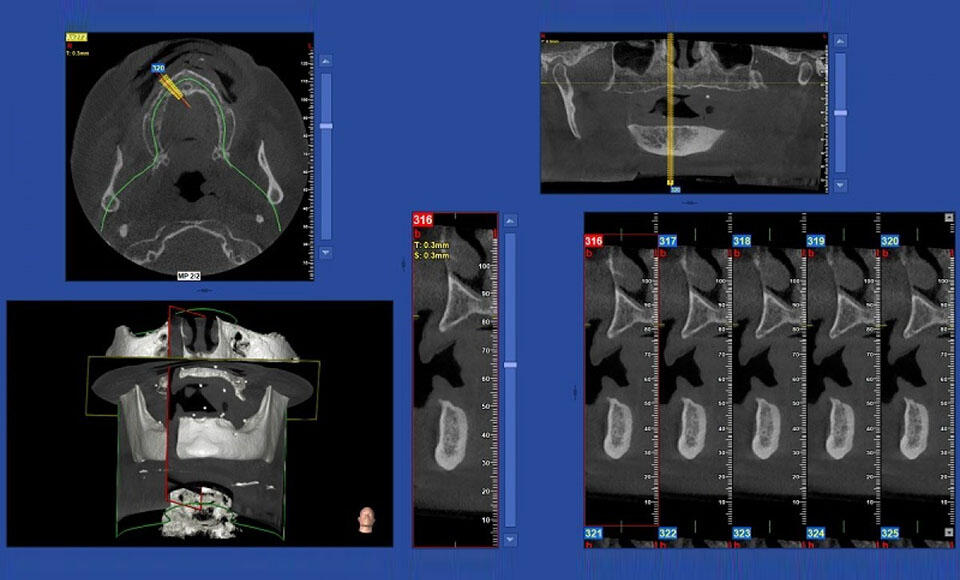

Diagnostica Cone Beam CT: NewTom ancora leader dell’innovazione

Con l’introduzione del NewTom 7G, l’azienda dimostra uno spiccato orientamento al miglioramento e all’innovazione continua nella diagnostica.

Cone Beam 3D: un insostituibile alleato per lo studio odontoiatrico

Le apparecchiature Cone Beam 3D (o Cone-Beam CT) si stanno diffondendo sempre di più negli studi odontoiatrici, portando notevoli benefici.

Cone-Beam 3D e piano di trattamento: i nuovi percorsi

Dalla 2D alla diagnostica 3D, imparare a dimenticare una visione diagnostica e apprenderne un’altra. L'esperienza di Daniele Benedetti Forastieri e del nostro Daniele Godi, apparsa sulla testata Odontoiatria33.